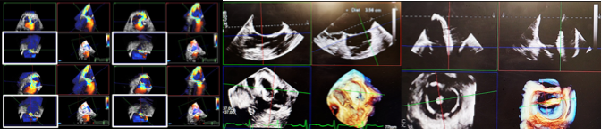

Advances in echocardiographic imaging have transformed the assessment and management of valvular heart disease, particularly in the current era of transcatheter structural interventions. The emergence of 4D transthoracic (TTE) and transesophageal echocardiography (TEE) technologies represents a major step forward, offering unprecedented detail in both anatomic reconstruction and hemodynamic evaluation.

A key innovation is real-time three-dimensional valve reconstruction, now achievable with markedly improved temporal and spatial resolution. High-density volumetric datasets allow clinicians to visualize complex valve morphology from multiple perspectives, providing a "surgeon's view" and "multi-axis view" of the mitral, tricuspid, and aortic valves. These capabilities are invaluable for pre-procedural planning and intra-procedural guidance in transcatheter interventions, where precise delineation of leaflet morphology, commissural orientation, and annular geometry directly impacts device selection, positioning, and procedural success.

Equally important is the application of multiplanar reconstruction (MPR) derived from 4D datasets. By extracting cross-sectional images from 4D datasets, clinicians can interrogate regurgitant orifices and flow convergence zones beyond the constraints of conventional two-dimensional imaging. Through MPR, quantification of regurgitant severity-including direct planimetry of the regurgitant orifice area and refined assessment of vena contracta area-can be performed with improved accuracy and reproducibility. In the context of mitral and tricuspid regurgitation, MPR facilitates integration with volumetric flow methods, thereby advancing quantification from semi-quantitative grading to more robust and physiologically meaningful measurements.